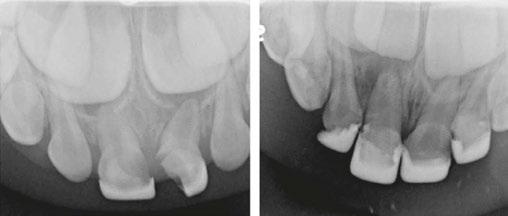

Case 2

A 3-year-old female presented with pulpal necrosis and abscess on #E and pulpal necrosis on #F. Extraction therapy or pulpectomy was offered. The family was highly motivated to retain #E and #F. The pulpectomy was performed with 0.02 K-Flex hand files, 3% NaOCl with a lateral vented needle, obturated with Vitapex (Neo Dental International Inc., Federal Way, Washington), a premixed paste of calcium hydroxide and iodoform. The access was filled with a HVGIC sealing the pulp therapy and increasing the clinical success by minimizing the potential for bacterial contamination. NuSmile ZR anterior crowns were selected as offering a full-coverage, esthetic, cemented restoration with no polymerization shrinkage when compared to a composite restoration. Crowns were cemented with NuSmile® BioCem (NuSmile, Houston, Texas). This is clinically beneficial as the provider would want to cement a restoration that provides limited microleakage minimizing the potential for bacterial contamination.15-17 At 6-month follow up, lesion healing had occurred with healthy gingival margins and no plaque accumulations (Figure 3).

A 4-year-old female presented with existing Silver Modified Atraumatic Restorative Technique (SMART) style restorations on #D, #E, #F, #G, and caries on other teeth. These anterior lesions

had been previously treated using SDF and covered with a HVGIC in a strip crown form. Though her lesions were stable from the clinical success of the SDF and HVGIC, these restorations were starting to fracture and demonstrate loss of material. The family wanted a more esthetic treatment option that would have a longer survivability. Additionally due to her high caries risk nature, a full coverage restoration with NuSmile® ZR anterior crowns were a more ideal solution in stabilizing her extensive decay pattern and covering staining from SDF therapy (Figure 4).

Figure 3: NuSmile® ZR Crowns were selected as a cementable full coverage restoration. At 6-month recall, apical tissues were healed with excellent gingival health Figure 4: SMART style restorations that were definitively restored with NuSmile® ZR Crowns as an esthetic option to cover SDF staining